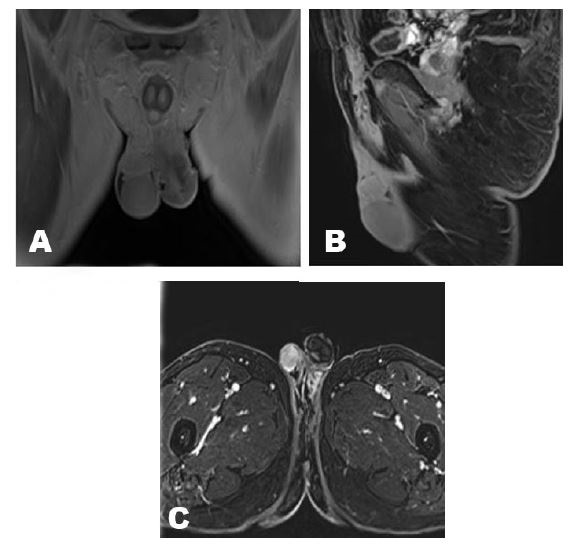

A 58-years-old Saudi male presented with two years history of right painless scrotal mass. There was no history of fever, genital trauma, genital infection, or tuberculosis (TB). The patient denied having nausea, vomiting, diarrhea, flushing, palpitations, or weight changes. On physical examination, the scrotum revealed a right-sided non-tender mass with 2 cm above and not attached to right testis. The left side of the scrotum was normal and no palpable lymph nodes. Normal tumor markers of testicular tumor. Ultrasonography revealed a well-defined, homogeneous, hyperechoic lesion measuring approximately 2 cm in the right extratesticular region.. It was seen superior to right testis and right epididymis and separable from them with high vascularity by Doppler study. Both testes appeared average in size and normal vascularity (Figure 1). Magnetic resonance imaging (MRI) with intravenous (IV) gadolinium contrast for abdominal and pelvis showed right extratesticular soft tissue mass not separable from the spermatic cord and there was no distant metastasis (Figure 2A, Figure 2B, Figure 2C). Based on images, provisional clinical diagnosis of a benign paratesticular mass was made and the patient underwent exploratory excision of the mass with preservation of cord and testis. The patient was discharged two days after surgery. Histopathology showed grossly a single soft gray light brown tissue mass measuring 2×2 cm with white firm focally fleshy cut surface. Microscopically, cells arranged in nested and trabecular growth pattern. The neoplasm is composed of tumor nests comprising of round cells with abundant granular eosinophilic-basophilic focally clear cytoplasm surrounded by sustentacular cells embedded in vascular rich stroma. The lesion exhibited no evidence of capsular invasion, lymphovascular invasion, a diffuse pattern, tumor necrosis, atypical mitosis, or increased mitotic activity. Histopathology reported this mass is paraganglioma.

Figure 2: (A–C) MRI showed right extratesticular soft tissue mass not separable from the spermatic cord.